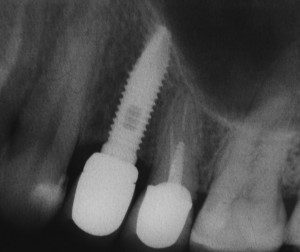

Рисунки 9, 10, 11. Рентгенограммы области имплантации: слева – до операции, в центре – сразу после операции имплантации в сочетании с закрытым синуслифтингом, справа – через 12 месяцев после протезирования.

Рисунок 12. Ортопантомограмма. К сожалению, по данному снимку сложно судить о пространственной конфигурации верхнечелюстной пазухи

Рисунок 13. Интерфейс программы конусно-лучевой компьютерной томографии. Именно КЛКТ дает наиболее полное представление о клинической ситуации и позволяет правильно спланировать оперативное вмешательство.

Ортопантомография подразумевает «перенос» трехмерной структуры в двухмерную проекцию, поэтому в ней неизбежны искажения. Планировать операцию по ортопантомограмме мы можем лишь приблизительно, буквально в пределах понятий «нужен синуслифтинг или нет».